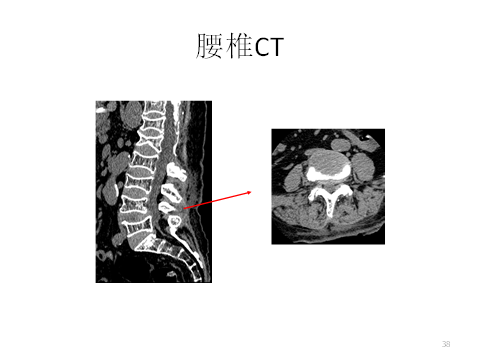

女性,71岁,主因腰部及双下肢疼痛半年,加重1月入院。患者半年前无明显诱因出现腰部疼痛,伴双下肢疼痛及左下肢麻木,范围为大腿外侧及小腿后外侧,休息后略缓解。1月前患者无明显诱因左下肢疼痛麻木明显加重,不能行走。保守治疗止疼药副反应明显。目前无法站立,VAS评分8分,ODI评分 64分。

既往史:溶血性贫血20余年,长期服用激素治疗,血色素正常。帕金森病10余年。7年前因T10压缩性骨折行PVP术。4年前胸部外伤致左第5-6肋骨折。

查体:脊柱后凸畸形。L5水平扣痛(+)。四肢肌张力高,可见不自主震颤。双下肢感觉、肌力、反射对称。双侧直腿抬高试验(-),双侧股神经牵拉试验(-)。

患者合并腰椎管狭窄症、帕金森病、骨质疏松症。考虑患者溶血性贫血,长期服用激素,骨质疏松严重,内固定禁忌明显,经讨论,决定予患者微创手术治疗。术后患者症状缓解明显。